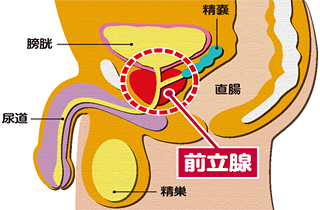

前立腺とは何ですか?

前立腺とは:膀胱の下で尿道を取り囲むようにあるクルミ大の臓器です。

はたらき:前立腺液を分泌し、精液の一部を作ります。

放射線治療の場合、がんのある前立腺のみに照射したいのですが、前立腺は上に膀胱、後ろに直腸が接しているため、従来の外部照射療法では前立腺だけでなく周辺の臓器にも多くの線量の放射線がかかってしまい、また密封小線源治療(シード治療)でもある程度の線量がかかってしまい、かかったところに有害事象(副作用)が出現していました。